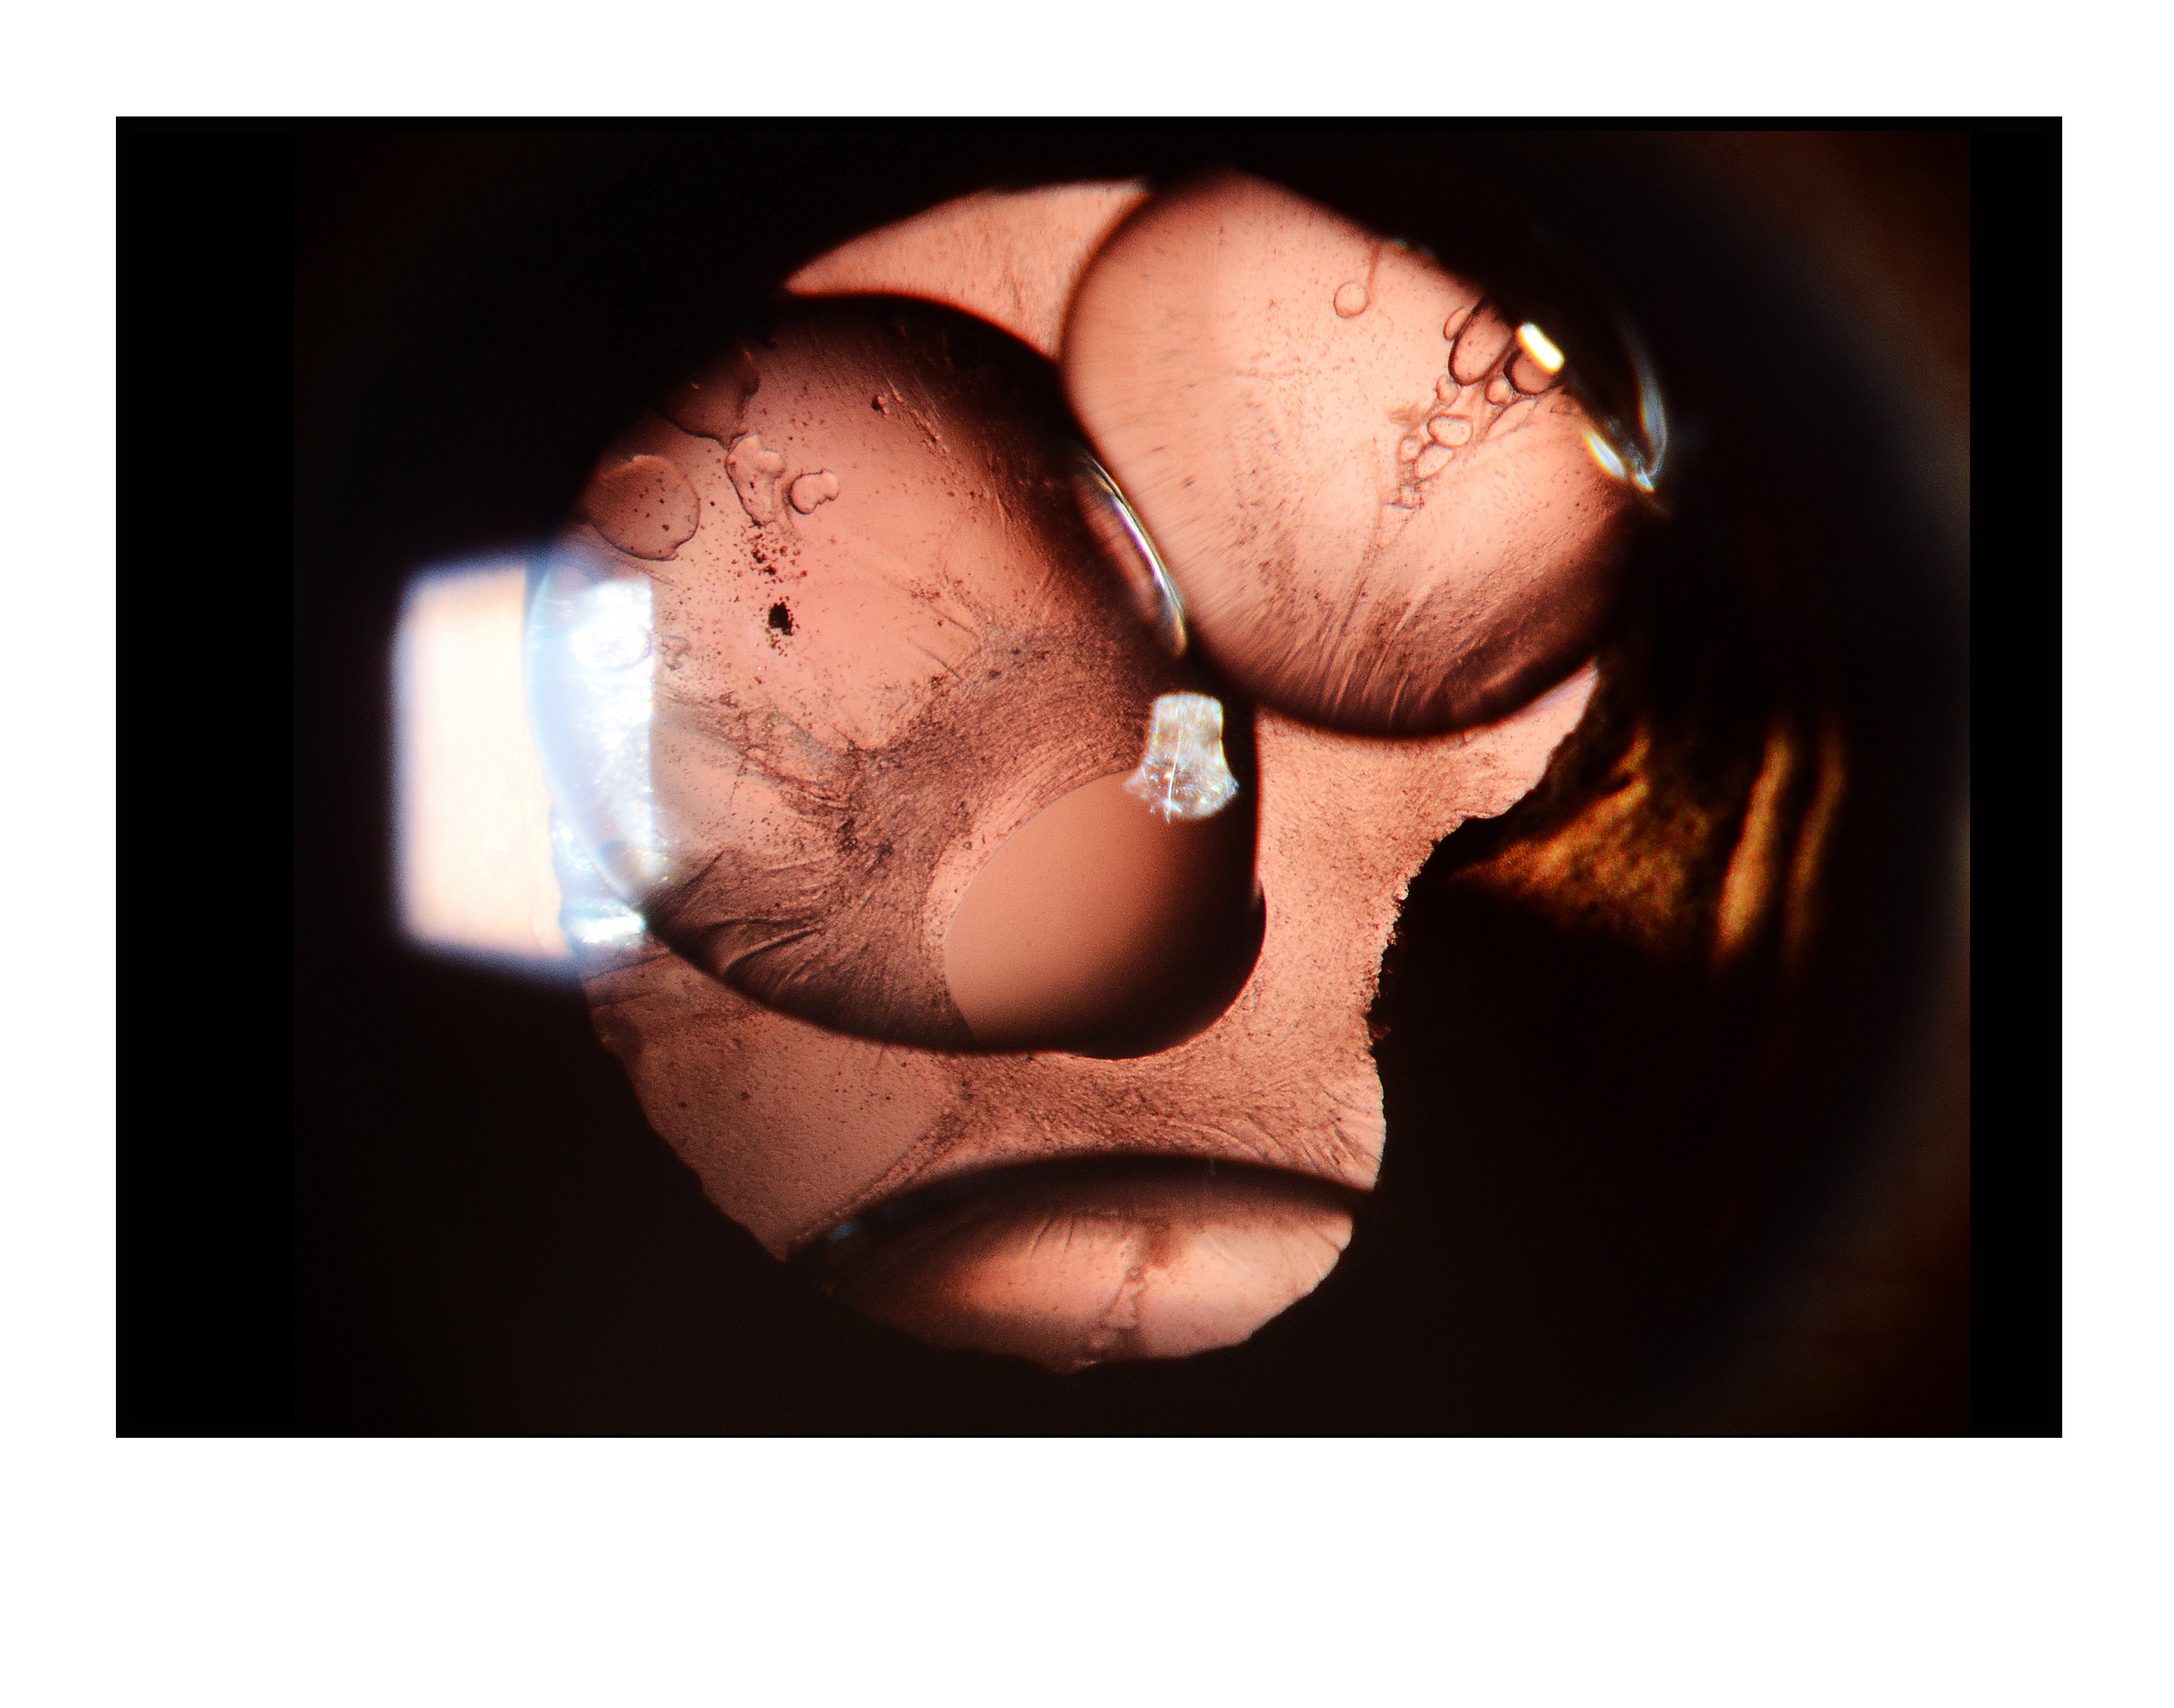

Gas Bubble Presented by Govinrajan Jayaraman This photograph received Honorable Mention in the category "Slit Lamp" and was displayed in the 2024 OPS Exhibit. Filed Under Cornea OPS Photo